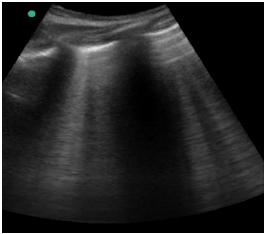

Um paciente de 40 anos de idade, vítima de queda de 9 metros (estava trabalhando quando o telhado cedeu), trazido à sala vermelha pelo SAMU, foi admitido com PA = 80 mmHg x 40 mmHg, FC = 120 bpm e tempo de enchimento capilar = 4 segundos. O emergencista procedeu ao e-fast, que evidenciou o achado apresentado na imagem.

Hemitórax direito superior

Hemitórax esquerdo superior

Insonação cardíaca Janela apical 5 câmaras com VTI de 9,08 cm

O nefrologista foi chamado a opinar na melhor conduta para o paciente. Para tanto, realizou uma ultrassonografia beira leito pulmonar e mensurou a velocidade integral tempo (VTI) do trato de saída do ventrículo esquerdo. Chegou, assim, à conclusão que poderia ser feita uma expansão no paciente. Com base nas imagens apresentadas, é correto afirmar que conduta recomendada pelo nefrologista está

A melhor conduta do emergencista nesse momento é